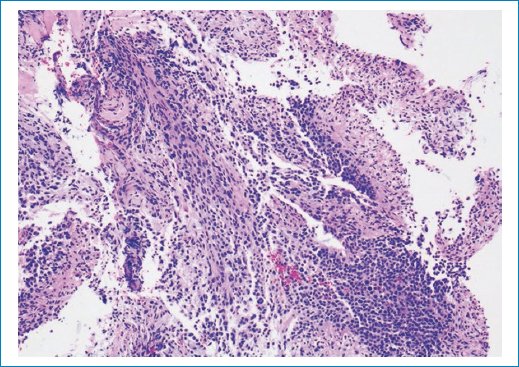

Imágenes de patología

El estudio histopatológico revela una neoplasia glial difusa, altamente celular, integrada por células tumorales con núcleos hipercromáticos y pleomorfismo moderados, con actividad mitótica aumentada. La inmunohistoquímica (IHQ) demuestra expresión difusa de proteína ácida fibrilar glial (GFAP), confirmando el origen glial.

Se observa positividad nuclear intensa y extensa para histona H3 K27M, hallazgo diagnóstico de glioma difuso de la línea media, H3 K27-alterado. El índice de proliferación evaluado mediante Ki-67 es elevado, en concordancia con un tumor de alto grado.

Análisis histológico

Las secciones de la muestra de biopsia, fijadas con formalina e incluidas en parafina, se tiñeron con hematoxilina-eosina (H&E) y se procesaron para IHQ con GFAP (EP672Y), p53 (DO-7), Ki-67 (30-9) (Roche/Ventana Medical Systems Inc., Tucson, AZ, EE.UU.) e histona H3-K27M (Millipore/Sigma, Burlington, MA, EE.UU.), como se describió previamente10.

La biopsia mostró una neoplasia infiltrante hipercelular compuesta por pequeñas células “azules” con núcleos redondos hipercromáticos y escaso citoplasma o, de forma más focal, por células fibrilares con núcleos hipercromáticos alargados (Fig. 7). El tumor mostró una actividad mitótica muy alta, con hasta 16 figuras mitóticas por campo de alta potencia (Fig. 8). La IHQ con anticuerpo Ki-67 mostró un índice de proliferación Ki-67 muy alto, hasta del 56%, en correlación con la actividad mitótica elevada (Fig. 9). El origen glial del tumor se estableció por IHQ con el marcador glial GFAP que mostró una tinción fuerte y difusa del citoplasma de la célula tumoral (Fig. 10), mientras que un carcinoma de mama metastásico fue descartado por IHC con anticuerpos keratin CAM 5.2 y GCDFP-15. El anticuerpo p53 mostró una regulación positiva en algunos núcleos de células tumorales dispersos, lo que no sugiere una mutación TP53. Por el contrario, la IHQ con un anticuerpo específico para la mutación histona H3 K27M mostró una expresión fuerte y difusa de la proteína mutante en los núcleos de las células tumorales, pero no en los núcleos no tumorales de la vasculatura (Fig. 11). Este resultado estableció el diagnóstico final de este tumor como glioma difuso de línea media, mutante de histona H3 K27M (DMG/K27M), grado 4 de la OMS.

Figura 7. La tinción hematoxilina-eosina muestra infiltración difusa del neuropilo por una neoplasia hipercelular compuesta por pequeñas células azules con núcleos redondos hipercromáticos; focalmente, se observan células fibrilares con núcleos alargados. Aumento de la imagen: 10x.

Figura 8. Aumento de la actividad mitótica. Preparación citológica intraoperatoria con hematoxilina y eosina que muestra frecuentes figuras mitóticas (flechas rojas). Imagen con aumento de 40x.

Figura 9. Índice de proliferación de Ki-67 muy alto. La inmunohistoquímica con anticuerpo Ki-67 muestra un índice de proliferación muy alto, en correlación con la alta actividad mitótica. Aumento de la imagen: 10x.

Figura 10. Origen glial. La inmunohistoquímica con anticuerpo GFAP, un marcador de tumores gliales, muestra una tinción citoplasmática intensa y difusa de las células tumorales. Aumento de la imagen: 20x. GFAP: proteína ácida fibrilar glial.

Figura 11. La mutación de la histona H3 K27M se detectó únicamente en las células tumorales. La presencia de la mutación se detectó mediante inmunohistoquímica con un anticuerpo específico para la mutación. Obsérvese la fuerte expresión nuclear en todas las células tumorales y la ausencia de expresión en las células vasculares no tumorales. Aumento de la imagen: 20x.